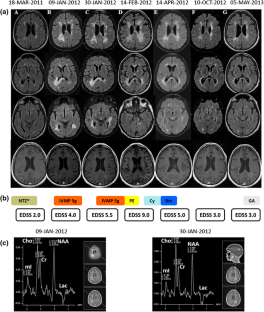

Fig. 1